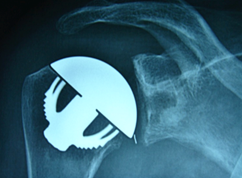

Dans certains cas les contraintes anatomiques liées à la rupture de vos tendons (coiffe des rotateurs) et aux dégâts osseux gléno-huméraux peuvent nécessiter le recours à une prothèse d’épaule semi-contrainte INVERSEE.